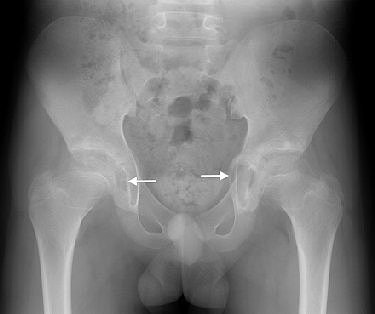

| Fourteen-year-old boy with camptodactyly-arthropathy-coxa vara-pericarditis (CACP) syndrome. Anteroposterior radiograph of pelvis shows smooth flattening of femoral heads and acetabulae are irregular. Initial cursory examination may suggest erosive change; however, presence of large acetabular cysts, particularly on the left (arrows) is virtually pathognomonic of CACP syndrome and is highly unusual in juvenile idiopathic arthritis. Note also bilateral coxa vara, which is a feature of condition. |

Periarticular osteopenia may appear on radiographs of CACP syndrome patients, but it is less pronounced than that seen with JIA. The syndrome also causes nonerosive arthropathy with smooth flattening of the affected joint surfaces, the authors stated.

Some highly distinguishing features of CACP syndrome are intraosseous fluid-filled herniations affecting the acetabulum that appear on x-rays as benign radiolucent acetabular lesions.

"The characteristically large acetabular cysts that occur in CACP syndrome are not seen in juvenile idiopathic arthritis," the authors noted. Also unlike JIA, the cervical spine in CACP syndrome remains normal.